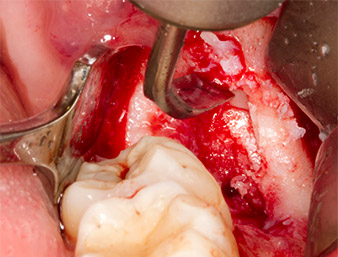

The tissue above the root remnant was not completely ossified and consisted for the most part of granulation tissue modified by inflammation (Fig. 4).

Granulation tissue

Fig. 4: Two Langenbeck retractors and a raspatorium expose the operating area. Granulation tissue of the incompletely healed first osteotomy can be seen.